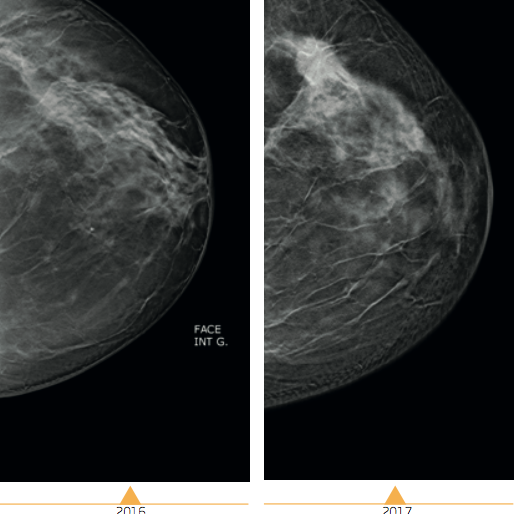

GYNECOMASTIE

La gynécomastie est un symptôme sans gravité à l’adolescence et elle régresse en général spontanément. La gynécomastie pathologique résulte d’un déficit androgénique ou d’une imprégnation estrogénique excessive : elle nécessite la recherche d’une cause endocrinienne, métabolique ou tumorale. DEFINITION La gynécomastie est un symptôme et non une maladie. Elle se définit comme hyperplasie des tissus…